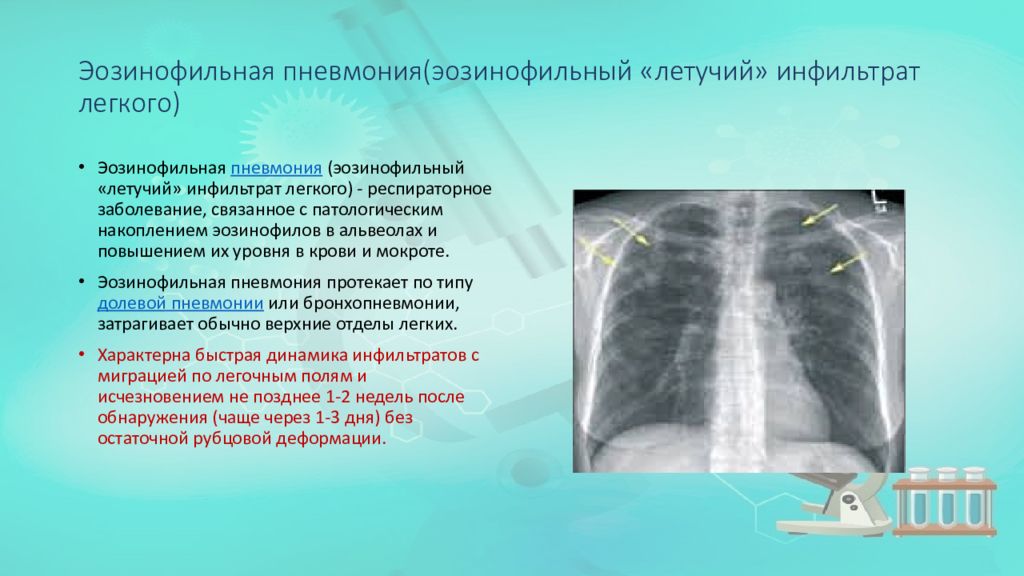

Рентгенологические изображения и синдромы патологии легких

Раздел: Кадры-подсказки